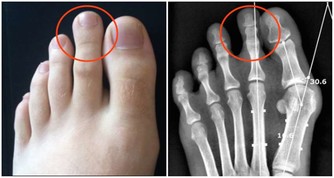

腿動脈栓塞以後,這部分腿部就會缺血,變得皮膚蒼白、溫度降低,甚至連足背動脈都可能摸不到了。